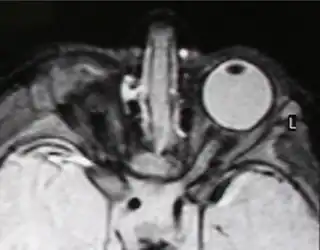

IRM de anoftalmía unilateral | ||

La anoftalmía es la ausencia completa de uno o ambos ojos. [1]

Cuando el ojo existe en el momento del nacimiento, pero está muy poco desarrollado, el término que se utiliza para referirse a esa situación es microftalmía. La microftalmía congénita es más frecuente que la anoftalmía.

Un estudio realizado en Inglaterra entre los años 1988 y 1994 mostró que la incidencia conjunta de ambos trastornos era de un caso por cada 10 000 nacimientos. Tanto la anoftalmía como la microftalmía congénita pueden ser unilaterales o bilaterales y suelen asociarse a una órbita poco desarrollada, ausencia de párpados y de la glándula lagrimal en la hemicara afectada.[2]